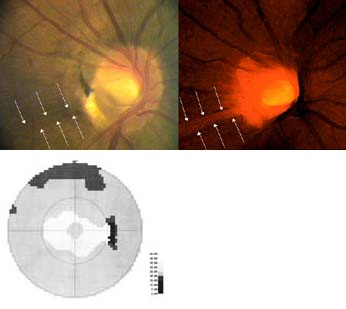

Výpadek proužku nervových vláken začíná temporálně dole od disku, kde je patrná peripapilární hemohagie. V zorném poli výpadku odpovídá horní paracentrální skotom.